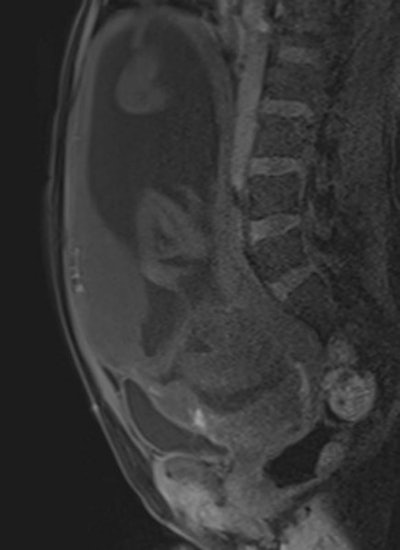

Axial T2-weighted single-shot fast spin-echo MR image shows an irregular outer uterine contour with discontinuity of the T2-hypointense myometrial layer in the anterior uterine segment. All images courtesy of Dr. Leonor Alamo.Their retrospective study included 25 pregnant women (mean age 35.16) -- 12 with histopathologically proven placental invasion and 13 without to act as a control -- who were investigated by prenatal MRI without IV contrast at three hospitals using three different 1.5-tesla MRI units (Magnetom Symphony, Siemens Healthcare; Intera, Philips Healthcare; Signa, GE Healthcare). The women underwent MR imaging between June 2007 and December 2009 after obstetrician referral for suspected placental invasion upon standard pregnancy ultrasound exams. The MRI protocols were similar and included T1-weighted volume interpolated gradient-echo MR sequences in the sagittal and axial plane, single-shot fast spin-echo T2-weighted MR sequences, and true fast imaging with steady-state precession in the axial, sagittal, and coronal planes.